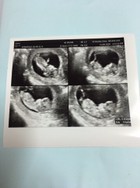

ซาวด์ครั้งแรกท้อง11วีคก้เจอแบบนี้เรยค่ะเสียใจกังวลมากค่ะอีก2อาทิตย์หมอนัดอีกเรายังมีหวังที่จะเจอตัวน้องยุไหมคะสอบถามแม่ๆที่เจอเรื่องแบบนี้หน่อยค่ะขอบคุณสำหรับคำตอบค่ะ😔

อันนี้พึ่งซาวด์ครั้งแรกเองค่ะ